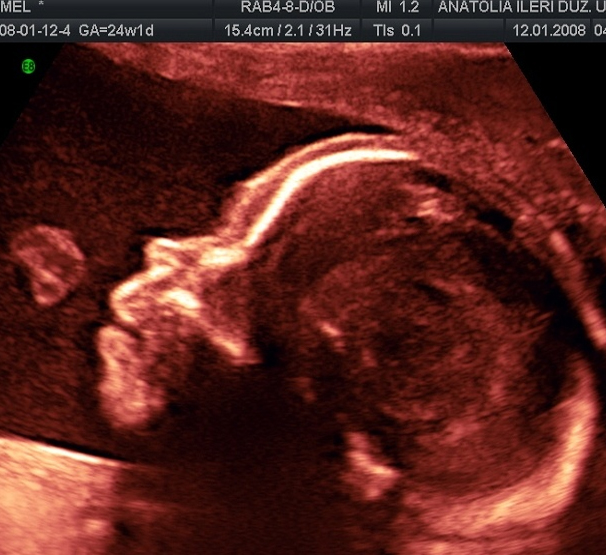

YÜZ PROFİL GÖRÜNTÜSÜ VE YUTKUNMA HAREKETİ

PARMAK EMME REFLEKSİ

OMURGANIN YAN PLANDA İNCELENMESİ

KULAĞIN GÖZLENMESİ

GÖĞÜS BOŞLUĞU VE KARIN İÇİ ORGANLARIN GÖZLENMESİ

DİZ VE AYAĞIN PROFİL GÖRÜNTÜSÜ

KAFA İÇİ (BEYİN) YAPILARININ DEĞERLENDİRMESİ